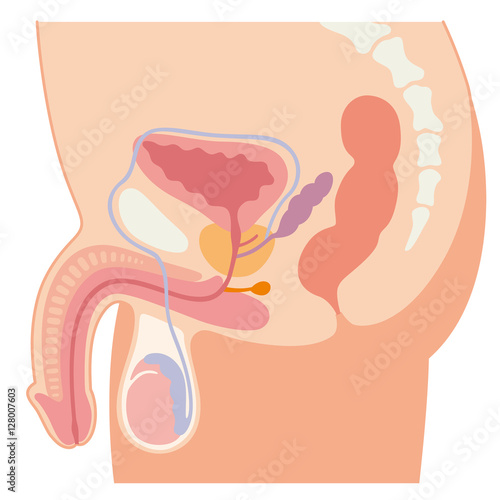

男性生殖器 断面図のイラスト素材

男性生殖器断面人体図 名称付き メディカルイラスト図鑑 無料の医療 美容素材集

男性生殖器 断面図のイラスト素材

男性生殖器断面人体図 名称付き メディカルイラスト図鑑 無料の医療 美容素材集

男性生殖器 断面図 Stock Illustration Adobe Stock

男性生殖器 断面図のイラスト素材

男性生殖器 断面図のイラスト素材